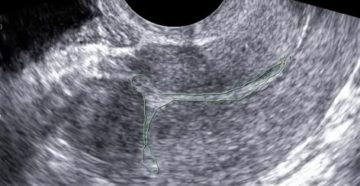

Чем опасно образование полипов матки в полости эндометрия у женщин В медицинском описании полипа упоминается,…